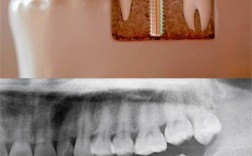

种植牙是一种通过外科手术的方式,将人工材料(通常是纯钛或钛合金)制成的种植体(类似牙根的结构)植入到缺牙部位的牙槽骨内,待种植体与牙槽骨紧密结合(这个过程称为“骨结合”)后,再在种植体上安装基台和牙冠,最终恢复牙齿的形态、功能和美观的修复方式。

- 种植体: 植入牙槽骨内的“人工牙根”,由生物相容性极佳的纯钛或钛合金制成,它负责替代天然牙根,为上面的修复体提供稳固的基础。

关键原理:骨结合

种植牙成功的核心在于骨结合,种植体植入牙槽骨后,在良好的愈合条件下,骨细胞会在种植体表面生长,最终与种植体表面形成牢固的、直接的生理性结合,就像天然牙根和骨头长在一起一样,这个过程通常需要3-6个月的时间。